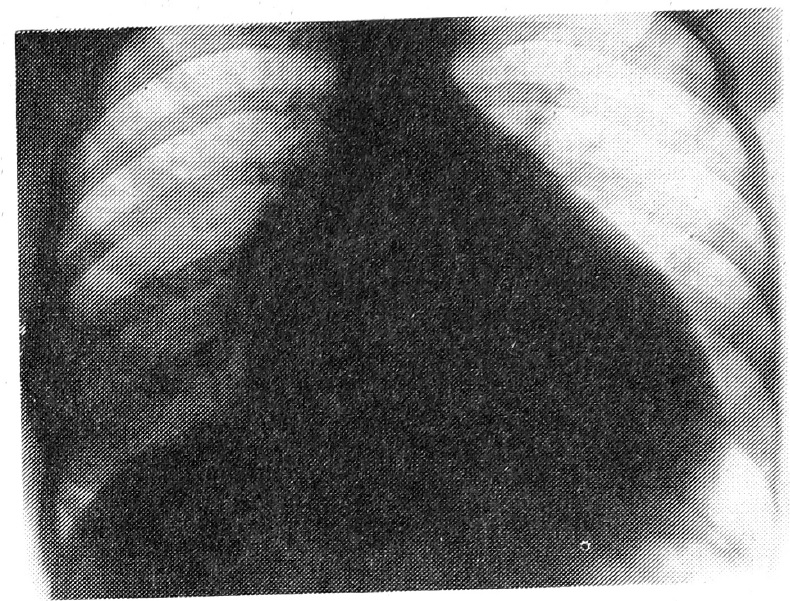

ЭХОКГ: конечный диастолический объем — 345 см3, ударный объем — 73 см3, фракция выброса—21%, дилатация всех полостей сердца с выраженным снижением сократительной функции, наличие перикардиального выпота (рис. 1).

Рис. 1. ЭХОКГ: дилатация всех полостей сердца.